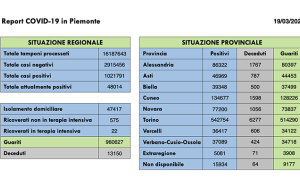

Aou di Novara, sono 50 i ricoverati covid

Sono 49 i ricoverati covid all'Aou di Novara, un decesso